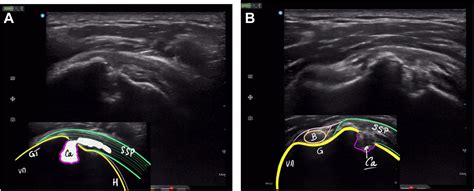

Ultrasound Useful for visualizing the surrounding soft tissue and identifying active inflammation.